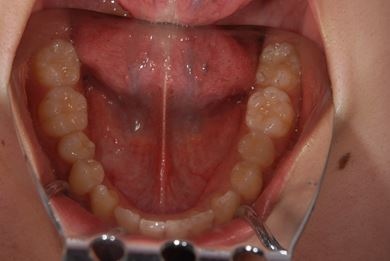

| 性別/年齢 | 女性 / 21歳 | ||||||||||||||||||||||||||||||||

| 主訴 | 歯の変色、欠けた部分を治したい。 | ||||||||||||||||||||||||||||||||

| 治療方針 | 上前歯を根管治療後、オールセラミッククラウンにて審美的回復を行う。 | ||||||||||||||||||||||||||||||||

| 治療内容 | オールセラミッククラウン2本(オールセラミック用土台2本) | ||||||||||||||||||||||||||||||||